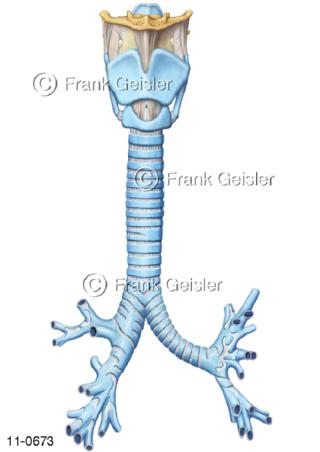

11-0673 Atemwege, Kehlkopf mit Luftröhre und Bronchien